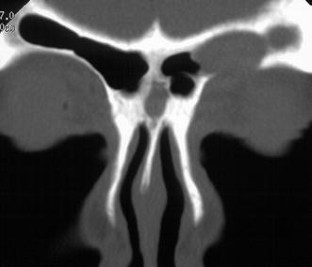

Fig. 3